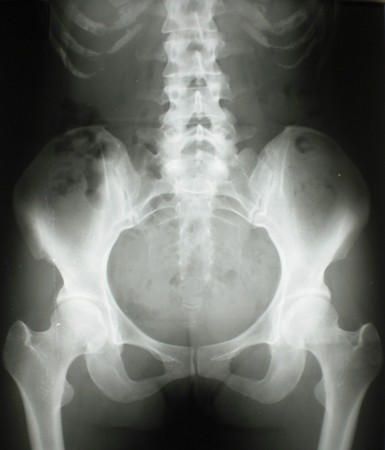

- 正常な骨盤

- 左右差がある骨盤

- 四角形骨盤

- 老化型骨盤

- 骨盤のレントゲン撮影 問診が終わったらレントゲン室へ。 土台と考えられる骨盤の歪みを真後ろからと真横からの2ポーズで撮影。 外見では解りずらい骨盤の歪みを探っていきます。